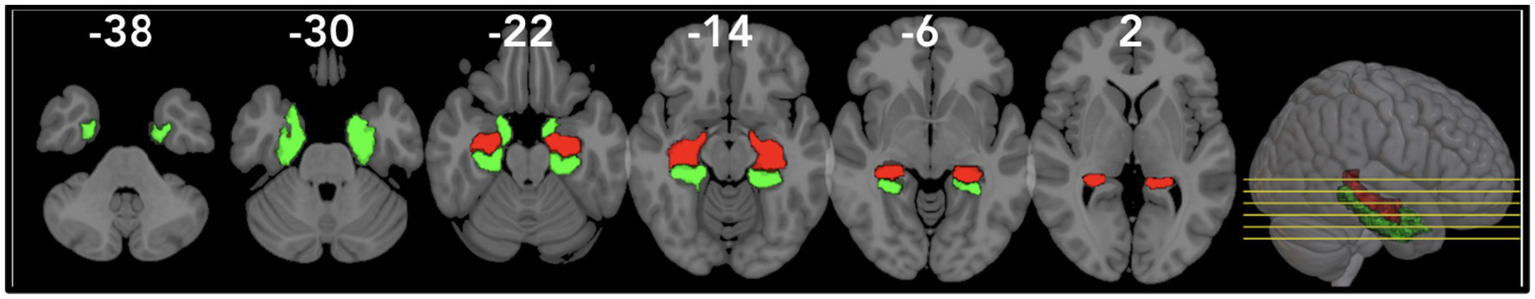

Based on prior rodent research, we predicted that hippocampal GMV would be a sensitive biomarker for neurodegenerative disorders and an indicator of cognitive function in our sample. Specifically, higher dietary fiber intake has been linked to improved cognitive performance, including faster information processing and better working memory (18). Our study builds on this by showing that a higher fiber-concentrated diet is associated with increased GMV in specific brain regions, particularly areas linked to cognition (19). Figure 4 illustrates this relationship, highlighting the right hippocampus and right parahippocampal gyrus as regions where GMV was significantly associated with fiber intake. Notably, previous research has often overlooked structural brain differences like GMV or localized areas influenced by dietary changes, making our findings significant as they specifically highlight the impact of fiber intake on GMV in localized brain regions, specifically the hippocampus.

Figure 4

Visualization of the right/left Parahippocampal Gyrus (rPHG/lPHG) and right/left Hippocampus (rHIP/lHIP) using the AAL3 atlas in MNI space. The rPHG/lPHG (red) and rHIP/lHIP (green) are shown in views to highlight their anatomical positioning.